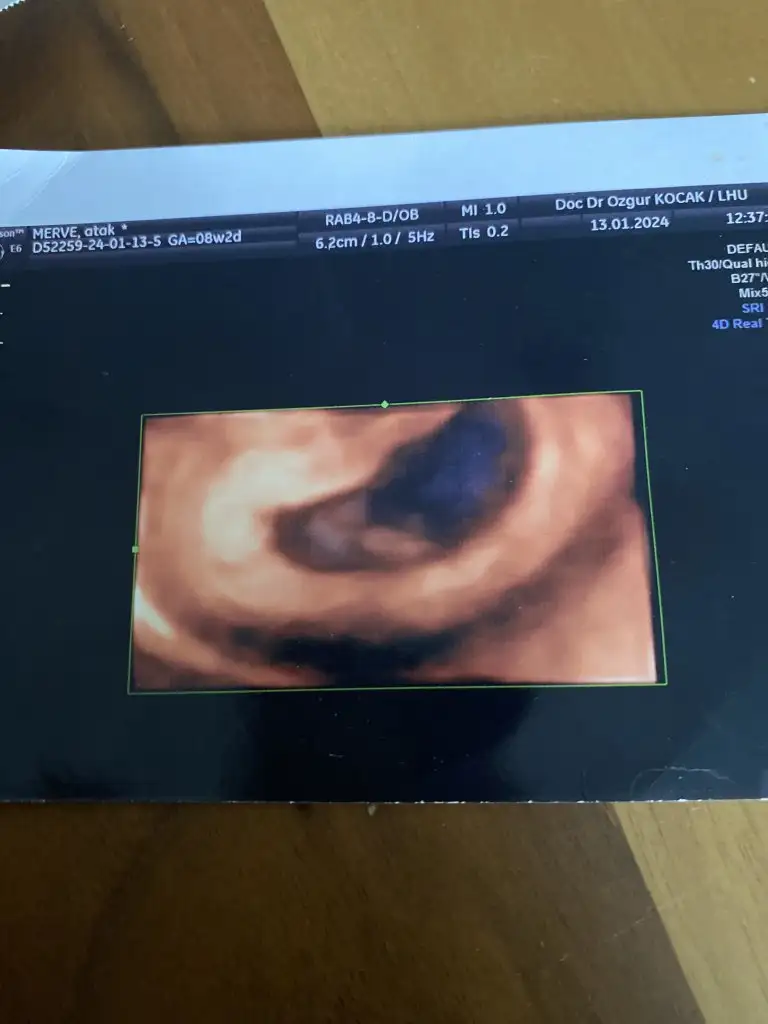

Canim banada tahminde bulunabilirmisin rica etsem.12+4 vaginal.Selam Kızlarbir çok kişi gruplardan beni bilir. Yine yetiştim imdatlara

5 ve 14. haftaya kadar olan ultrason fotolarınızı paylaşın. Vajinadan mı yoksa karından mı çekildiğini ve kaç haftalık olduğunu da mutlaka belirtin.